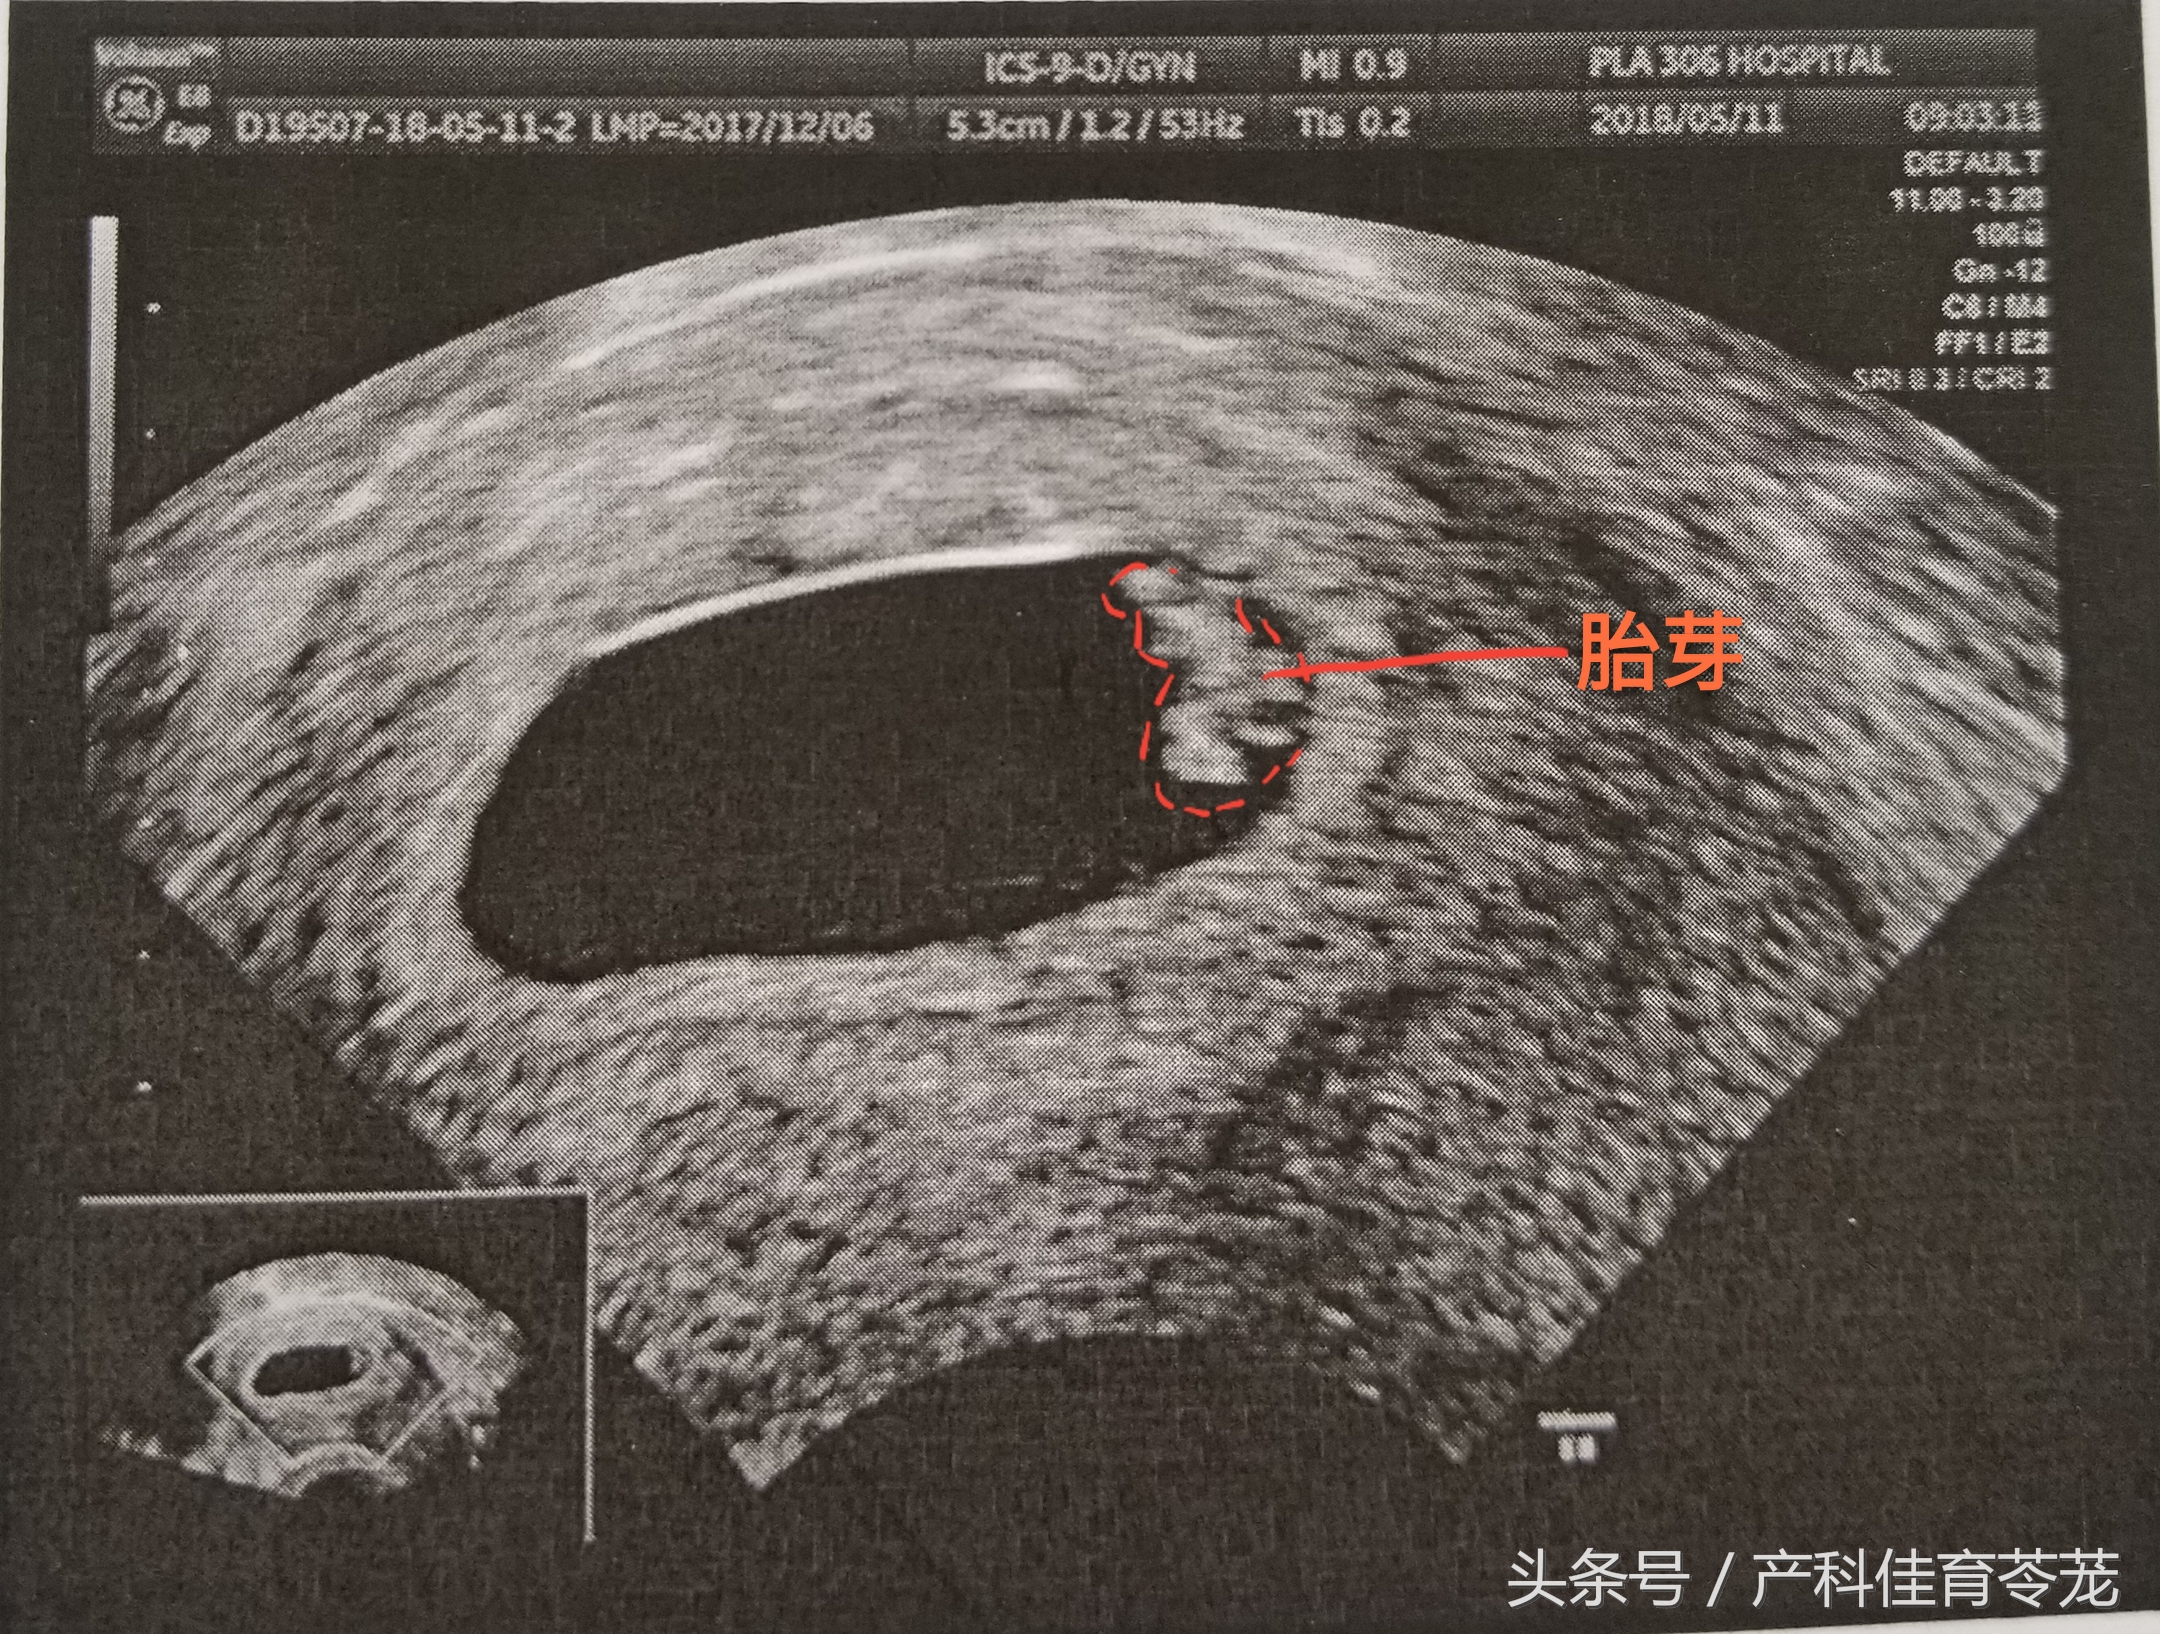

三、胎芽(Fetal Pole)

b超的3组数字代表什么,b超图片上的数字

只有出现胎芽,才能明确是宫内妊娠。

胎芽的增长速度为1mm/d,到妊娠53天时可以长到12mm。

胎芽长度达2mm或以上就可以看到胎心搏动,但也有5-10%的2-4mm的胚胎仍然看不到明显的胎心搏动。

胎芽的长度可以用来推算妊娠时间,准确率在3天之内:

妊娠天数=胎芽长度(mm)+42